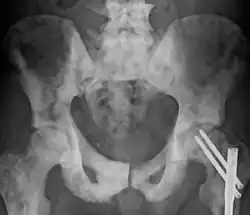

L’ostéosclérose est une affection osseuse qui se caractérise par un accroissement de la densité osseuse trop importante. Elle survient souvent à la suite d'une lésion ou d'une fracture de l'os, mais peut également être causée par des inflammations osseuses, un cancer des os ou par l'arthrose.

Son diagnostic s'effectue grâce à des symptômes caractéristiques (excroissance osseuse, fragilité osseuse, douleurs), qui sont confirmés par des examens radiologiques.